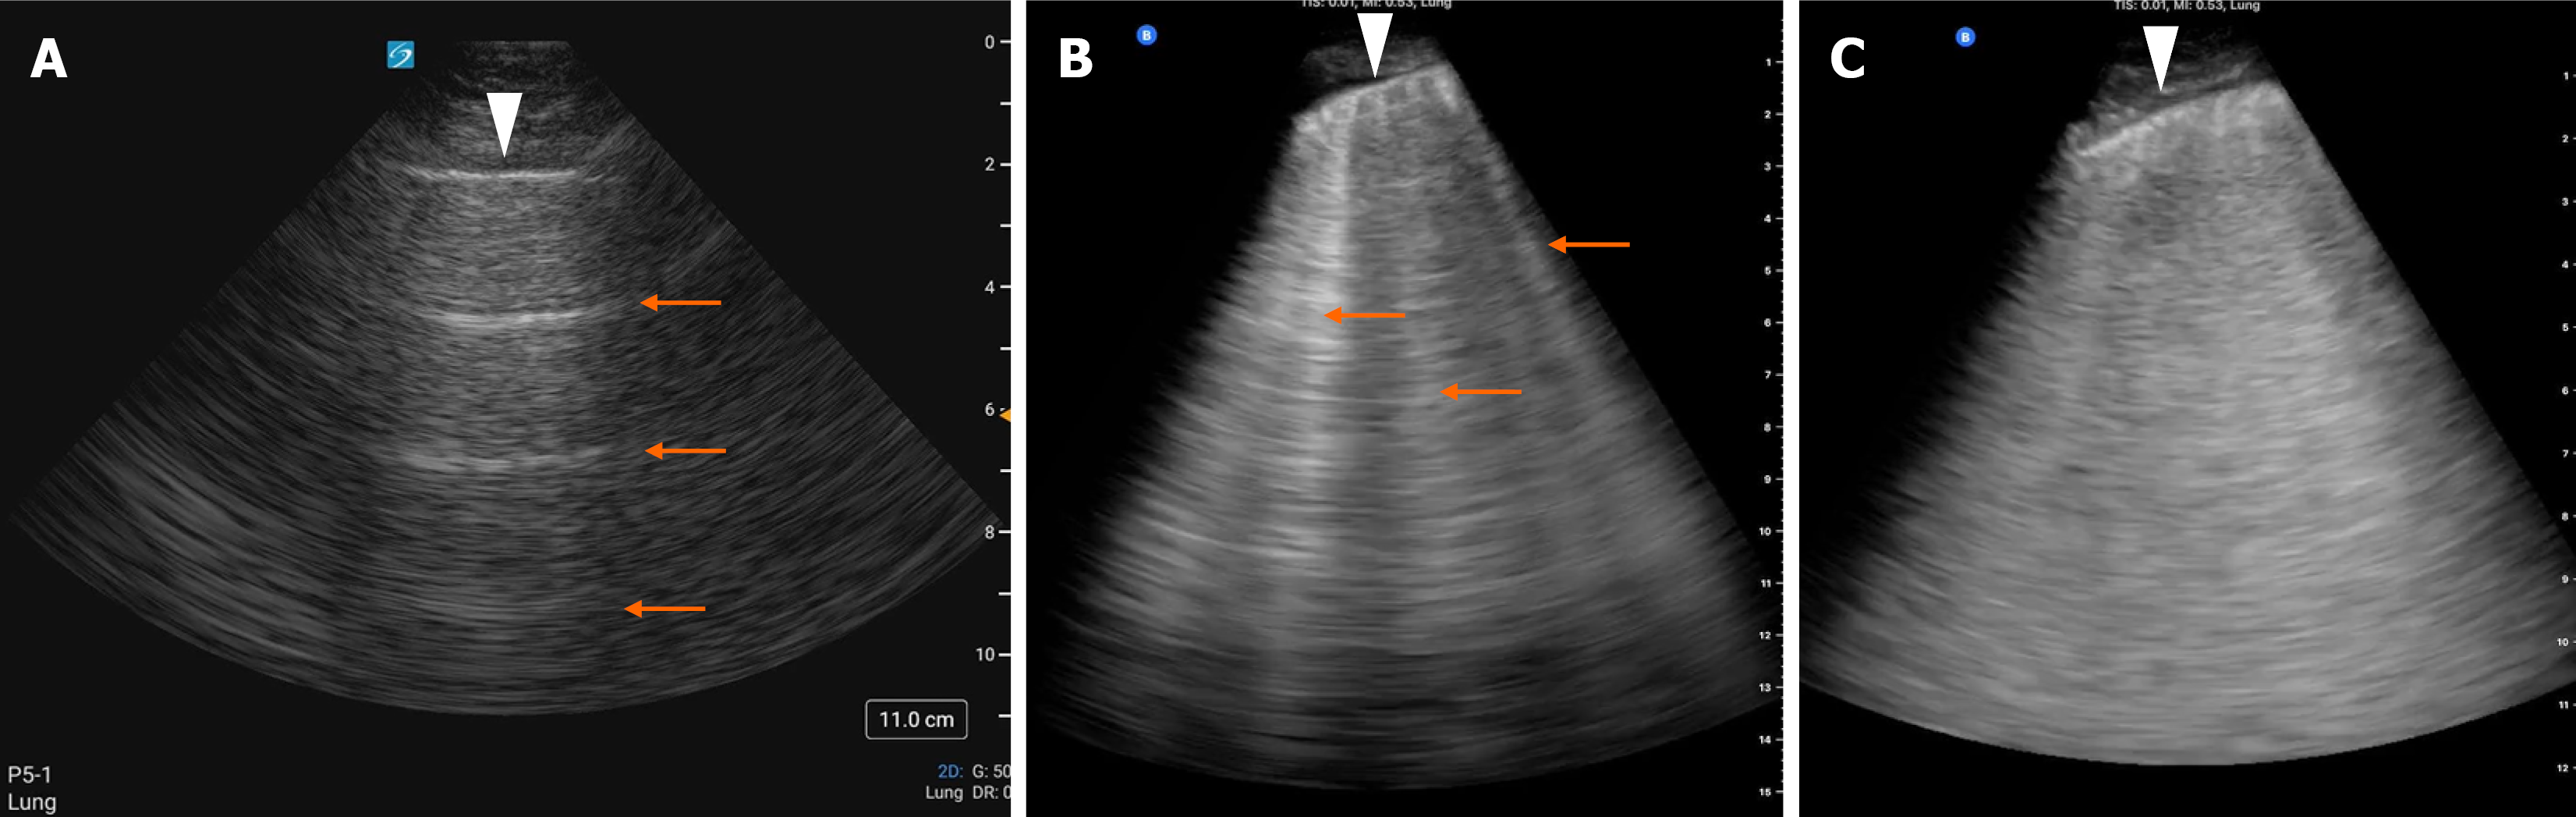

In a well-aerated lung, ultrasound reveals a bright horizontal pleural line that moves with respiration, a finding known as pleural sliding. A-lines, which are repeating horizontal artifacts, typically appear at regular intervals and are seen in this context (Figure 2A). These reverberation artifacts result from the repeated reflection of ultrasound waves between two strong reflectors, namely the pleural line and the ultrasound probe. The presence of A-lines indicates normal lung aeration and is characteristic of healthy lungs or non-interstitial conditions such as obstructive airway diseases or pneumothorax. In pneumothorax, however, pleural sliding is absent[15,16].

Figure 2

Figure 2 Lung ultrasound images showing. A: Normal horizontal artifacts known as A-lines (indicated by arrows); B: Discrete B-lines (arrows); C: Confluent B-lines creating a white-out appearance in the scanned lung zone typically seen in alveolar edema. The arrowhead in each image indicates the pleural line.

When the underlying lung becomes denser due to the replacement of air with fluid, blood, collagen, or other material, the acoustic mismatch between the pleura and lung tissue decreases. This change enhances the transmission and reflection of ultrasound waves, leading to the generation of vertical artifacts known as B-lines. These ‘ring-down artifacts’ result from the to and fro movement of the ultrasound beam within the altered lung parenchyma and are indicative of interstitial or alveolar involvement (Figure 2B and C)[15]. These are vertical, laser-like hyper-echoic artifacts that extend to the bottom of the screen without fading, moving synchronously with lung sliding. The appearance of multiple B-lines (three or more per intercostal space) in each zone is considered pathologic and indicates increased lung density or EVLW[15,16].